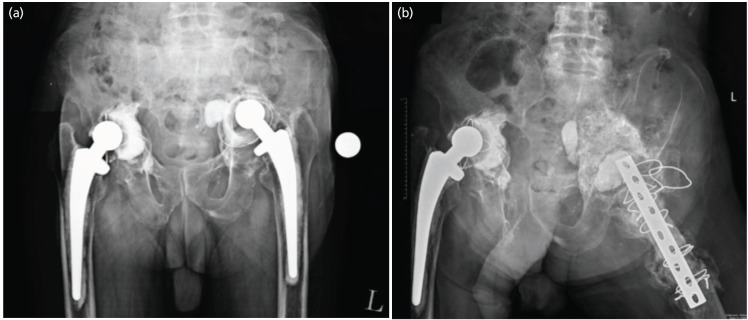

全髋关节置换术(THA)翻修手术中骨丢失的修复具有挑战性。髋臼嵌塞骨移植(AIBG)可以恢复骨存量和正常的髋关节生物力学。AIBG通常作为髋关节假体植入的单阶段手术进行,因为传统上认为,足够的阻生移植物负荷对于与宿主骨融合是必要的,从而防止骨吸收。我们提出一个73岁的绅士谁提出了双侧髋关节疼痛和减少活动。他被诊断为左侧THA无菌性松动伴髋臼突出,随后使用辐照的同种异体股骨头移植物进行了两期AIBG。第一阶段在没有髋臼负荷的情况下进行,但同种异体移植物成功地与宿主骨结合。这是首次报道的两期AIBG病例,表明同种异体移植物与宿主骨融合可能不需要髋臼负荷。因此,必要时,AIBG可以分两阶段进行,特别是在复杂的髋关节翻修手术和骨存量差的患者中。

Restoring bone loss in revision Total Hip Arthroplasty (THA) surgery is challenging. Acetabular impaction bone grafting (AIBG) allows the restoration of bone stock and normal hip biomechanics. AIBG is usually performed as a single-stage surgery with hip component implantation, as it is traditionally believed that adequate loading of the impacted graft is necessary for integration with the host bone thus preventing bone resorption. We present a case of a 73-year-old gentleman who presented with bilateral hip pain and reduced mobility. He was diagnosed with left THA aseptic loosening with acetabular protrusion and subsequently underwent a two-stage AIBG using irradiated femoral head allografts. The first stage was performed without acetabular loading, yet the allograft successfully integrated with the host bone. This is the first reported case of a two-stage AIBG demonstrating that acetabular loading may not be required for allograft integration to host bone. Therefore, AIBG may be performed as a two-stage procedure, when necessary, especially in the setting of complex revision hip surgeries and patients with poor bone stock.